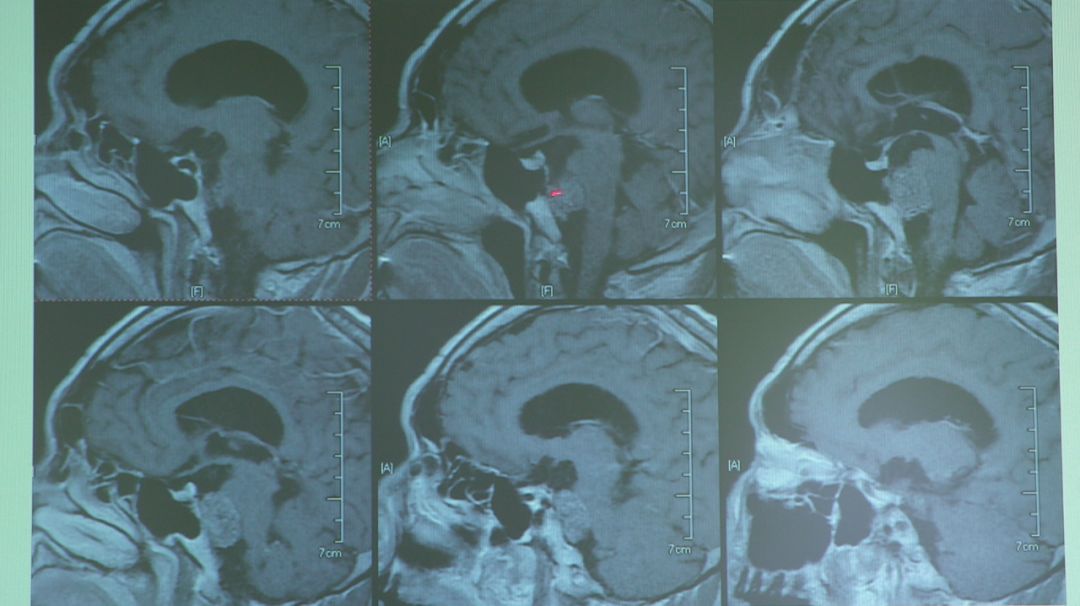

张亚卓是天坛医院的神经外科医生,从医至今他做过超过6000台脑外科手术。

张亚卓医生曾经完成过不少高技术含量的手术。

其中一起,患者的脑脊索瘤占据了大脑的四分之一,大到几乎把颅底脑干的全程压瘪了。

这个病症非常罕见,手术难度也非常大。

就连从医35年的张亚卓都只见过几次。

对于这种手术有人会选择放弃,而他却选择迎难而上。

医生们一起研究讨论病情,在术前也反复确定手术方案,因为他们知道不能错,面对罕见病症他们更需要打起12分精神。

最终手术成功,亲人们都激动到流泪。